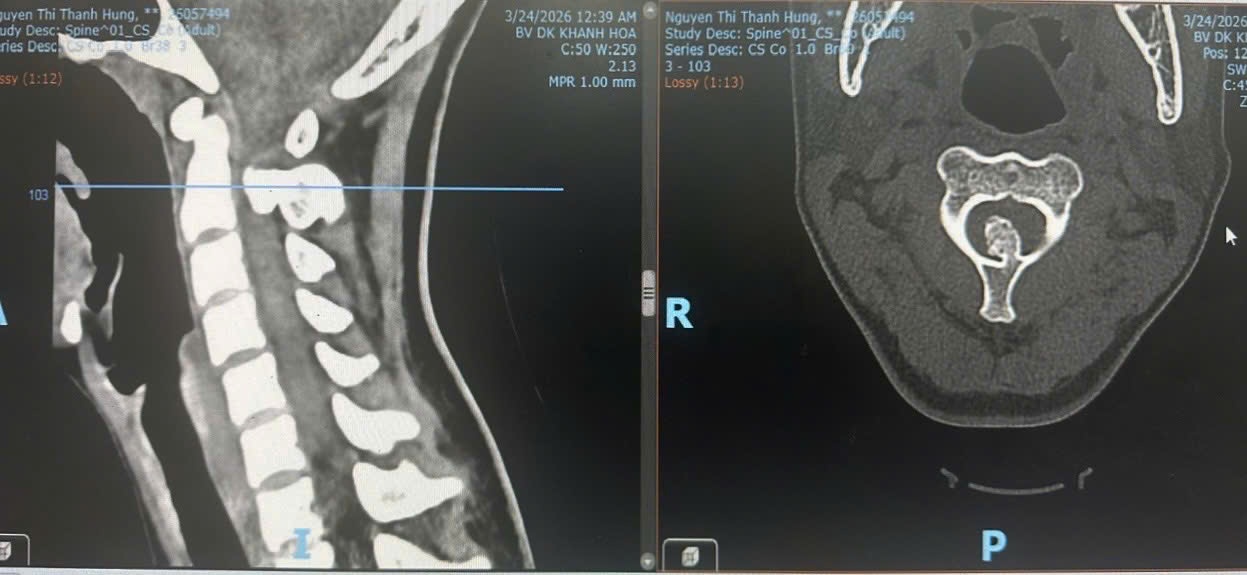

![]() |

| Hình ảnh chụp chiếu khối u xương đốt sống cổ chèn ép tủy sống |

Qua thăm khám, bác sĩ ghi nhận bệnh nhân T. đau cổ nhiều, tê tứ chi, bí tiểu, liệt vận động tứ chi không hoàn toàn, trong đó, tay chân trái bị liệt, tay chân phải còn nhấc lên được nhưng yếu. Kết quả từ các kỹ thuật cận lâm sàng cho thấy tủy cổ bị chèn ép rất nặng tại đốt sống cổ thứ 2 do khối u xương xâm lấn vào ống sống. Bệnh nhân được chỉ định phẫu thuật cấp cứu. Các bác sĩ đã thực hiện phẫu thuật bằng phương pháp mổ ít xâm nhập, sử dụng kính vi phẫu với đường mổ nhỏ khoảng 4 cm. Ê-kíp phẫu thuật tiến hành chẻ dọc gai sau đốt sống cổ thứ 2, cắt các mảnh gai sau ra khỏi bản sống, bảo tồn các cơ cổ sâu, sau đó cắt bán phần bản sống cổ thứ 2 và cẩn trọng lấy trọn khối u, không làm tổn thương tủy sống. Sau phẫu thuật 12 giờ, tình trạng bệnh nhân T. cải thiện rõ rệt, mức độ tê tứ chi giảm khoảng 50%, bệnh nhân có thể nhấc tay chân lên dễ dàng hơn.